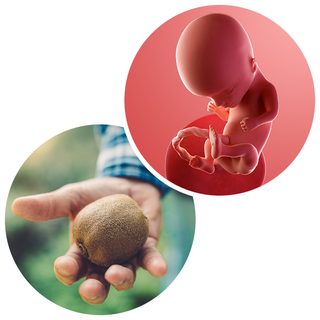

Your baby, or foetus, is around 8.5cm long from head to bottom, which is about the size of a kiwi fruit. The head is getting rounder and more in proportion with the rest of the body.